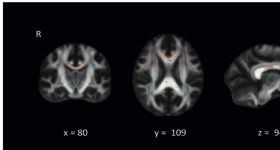

海馬在睡眠相關(guān)的記憶加工中扮演關(guān)鍵的角色,但目前尚不清楚海馬決定哪些特定的睡眠特征。針對(duì)局灶性雙側(cè)海馬...